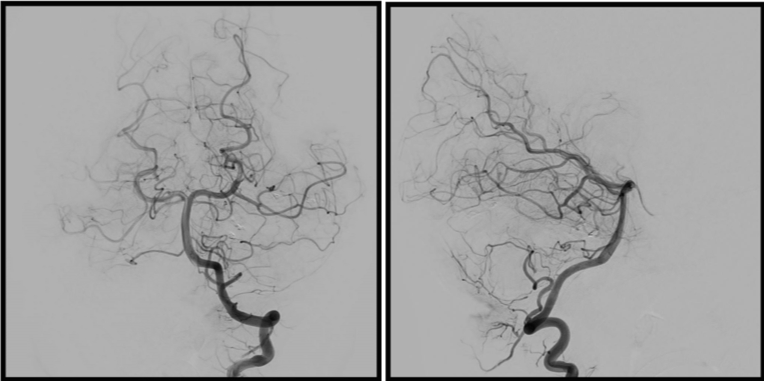

術前の造影写真です。〇内に脳動静脈奇形が描出されています。

塞栓術および摘出術後の造影写真です。脳動静脈奇形は消失しております。